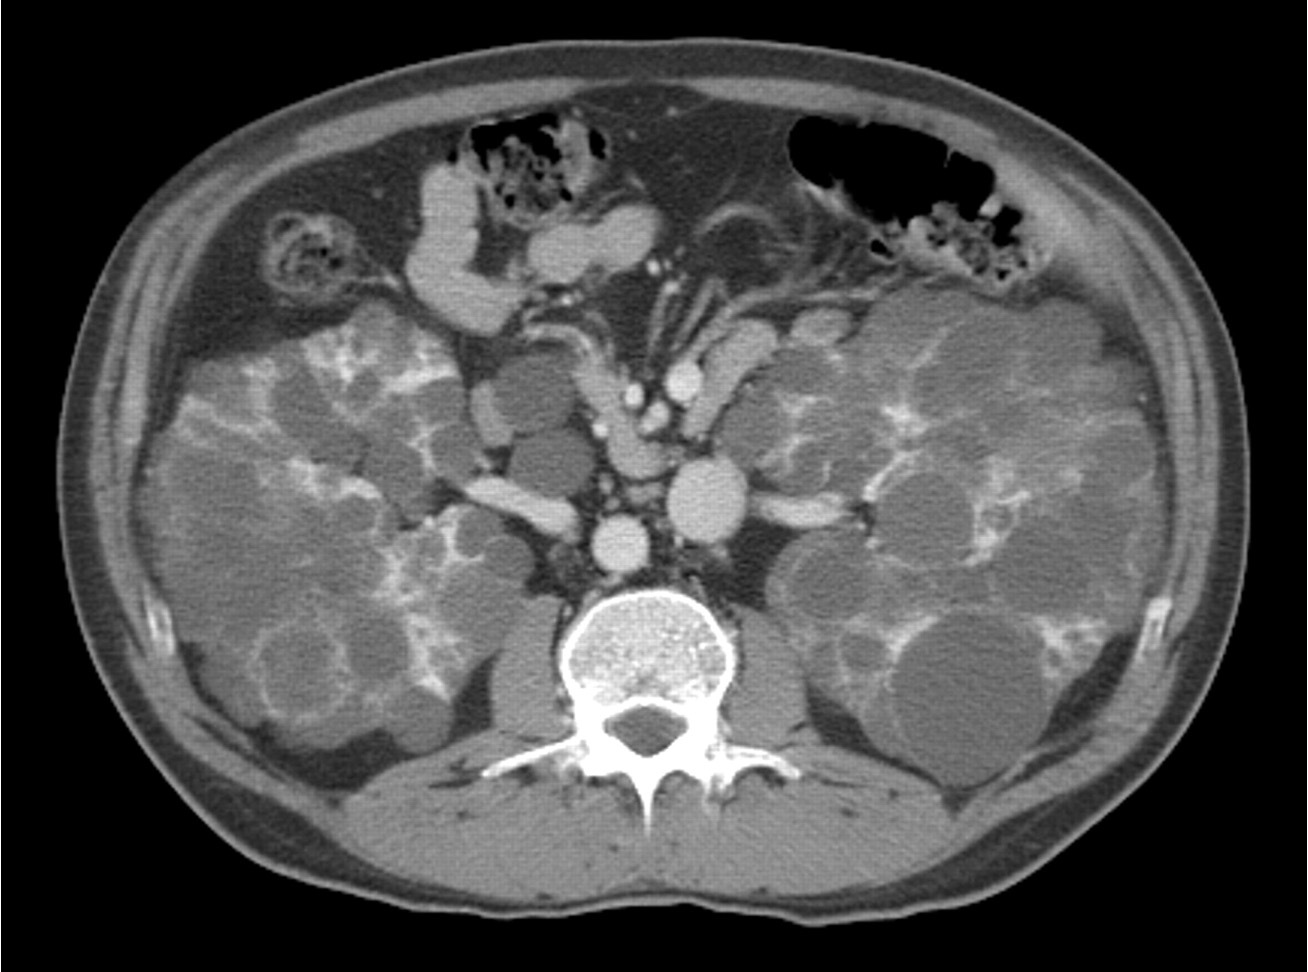

Autosomal Dominant Polycystic Kidney Disease

Autosomal dominant polycystic kidney disease ## Footnote CT of the abdomen (coronal reformats) demonstrates both kidneys to be markedly enlarged by innumerable cysts ranging in size from a few millimetres to multiple centimetres. These cysts also vary in density: most are near-water density, some are hyperdense, others are calcified. Also present are numerous cysts in the liver. The pancreas is unremarkable. Features are consistent with autosomal dominant polycystic kidney disease, which was subsequently confirmed.